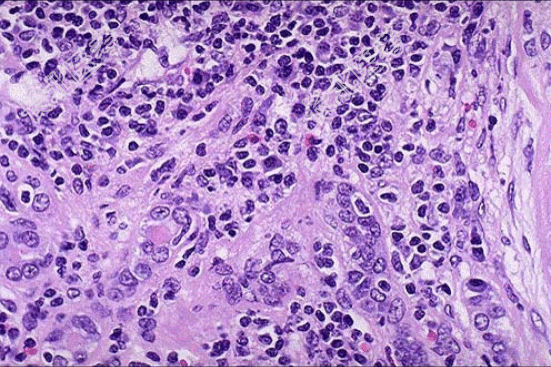

- [材料题] 患者女性,53岁,双肾缩小,表面可见不规则瘢痕,两侧改变不对称,切开,皮髓质界限不清,肾乳头萎缩,肾盏和肾盂因瘢痕收缩而变形,肾盂黏膜粗糙;巨检如图,镜下如图所示。

- 简答题1、应首先考虑的是?